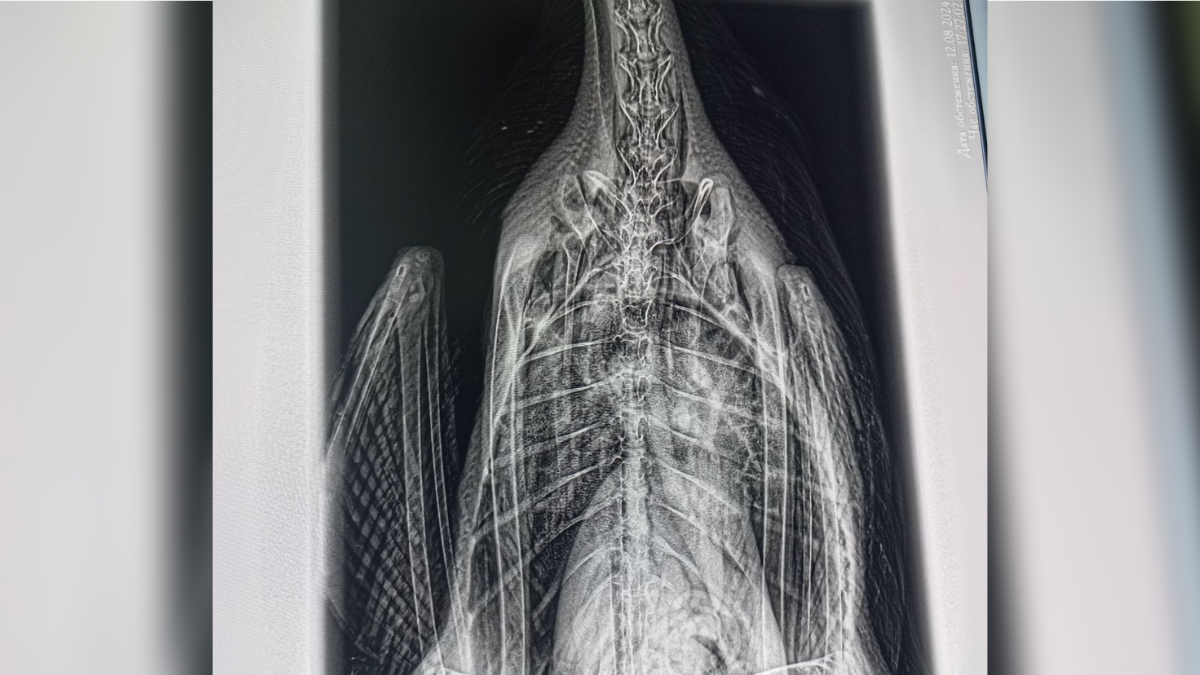

Небайдужий понад дві години намагався зловити пораненого птаха, аби надати йому допомогу. І ось, йому нарешті вдалося це зробити. Лебедя доставили в одну з ветеринарних клінік міста, де лікар обробив рану. Також на місці пернатому провели рентген, аби пересвідчитися у тому, що лебедь не ковтав снасті. Та ветеринар виявив на знімку птаха аспергільоз.

Аспергільоз - захворювання, до якого схильні птахи всіх видів. Викликається грибком роду аспергіллус, який широко поширений у ґрунті та потрапляє в організм шляхом вдихання спор, що підіймається у повітря від зараженої поверхні. Збудником хвороби є цвілевий грибок роду аспергіллус. Як зазначив журналістам ветеринар, який проводив огляд лебедя, основним джерелом зараження міг стати цвілий хліб, яким птахів на озері Руфа годують місцеві.

Лікування цієї хвороби довге та складне, адже лебедю треба щодня давати ліки, які самостійно птиця пити не буде. Головна складність для молодого птаха виникне при спробі злетіти, адже його легені не функціонуватимуть на повну.